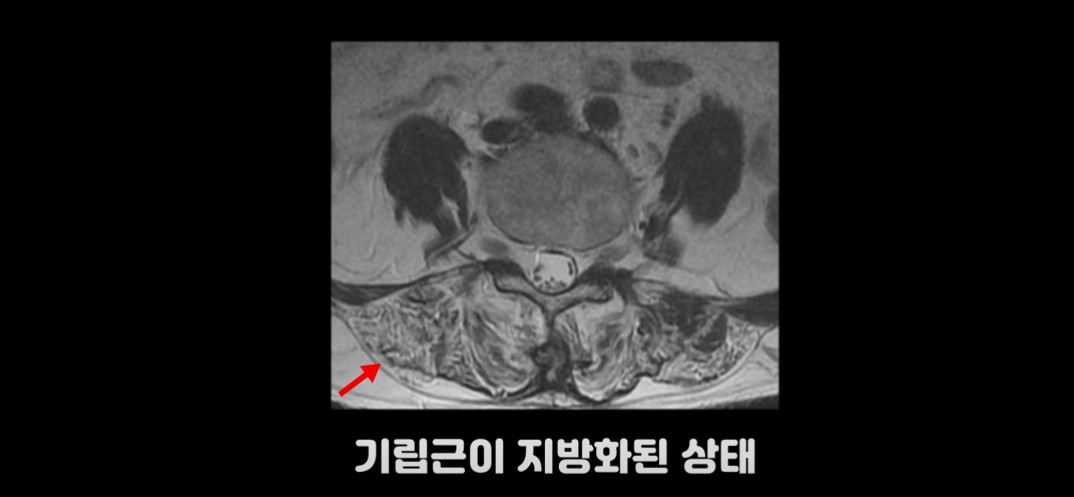

여기 허리가 많이 구부러지는 70세 이후 환자분의 MRI를 보시겠습니다.

이 환자분의 기립근을 보면 MRI상 어둡게 보여야 할 근육이 사진에서 보는 것 같이 하얗게 보입니다. 근육이 지방으로 변해 버린 겁니다. 또 근육의 크기도 위축되어 많이 작아져 있습니다.

기립근이 정상적인 상태의 MRI 사진과 비교해 보면 확연하게 차이를 느끼실 겁니다.